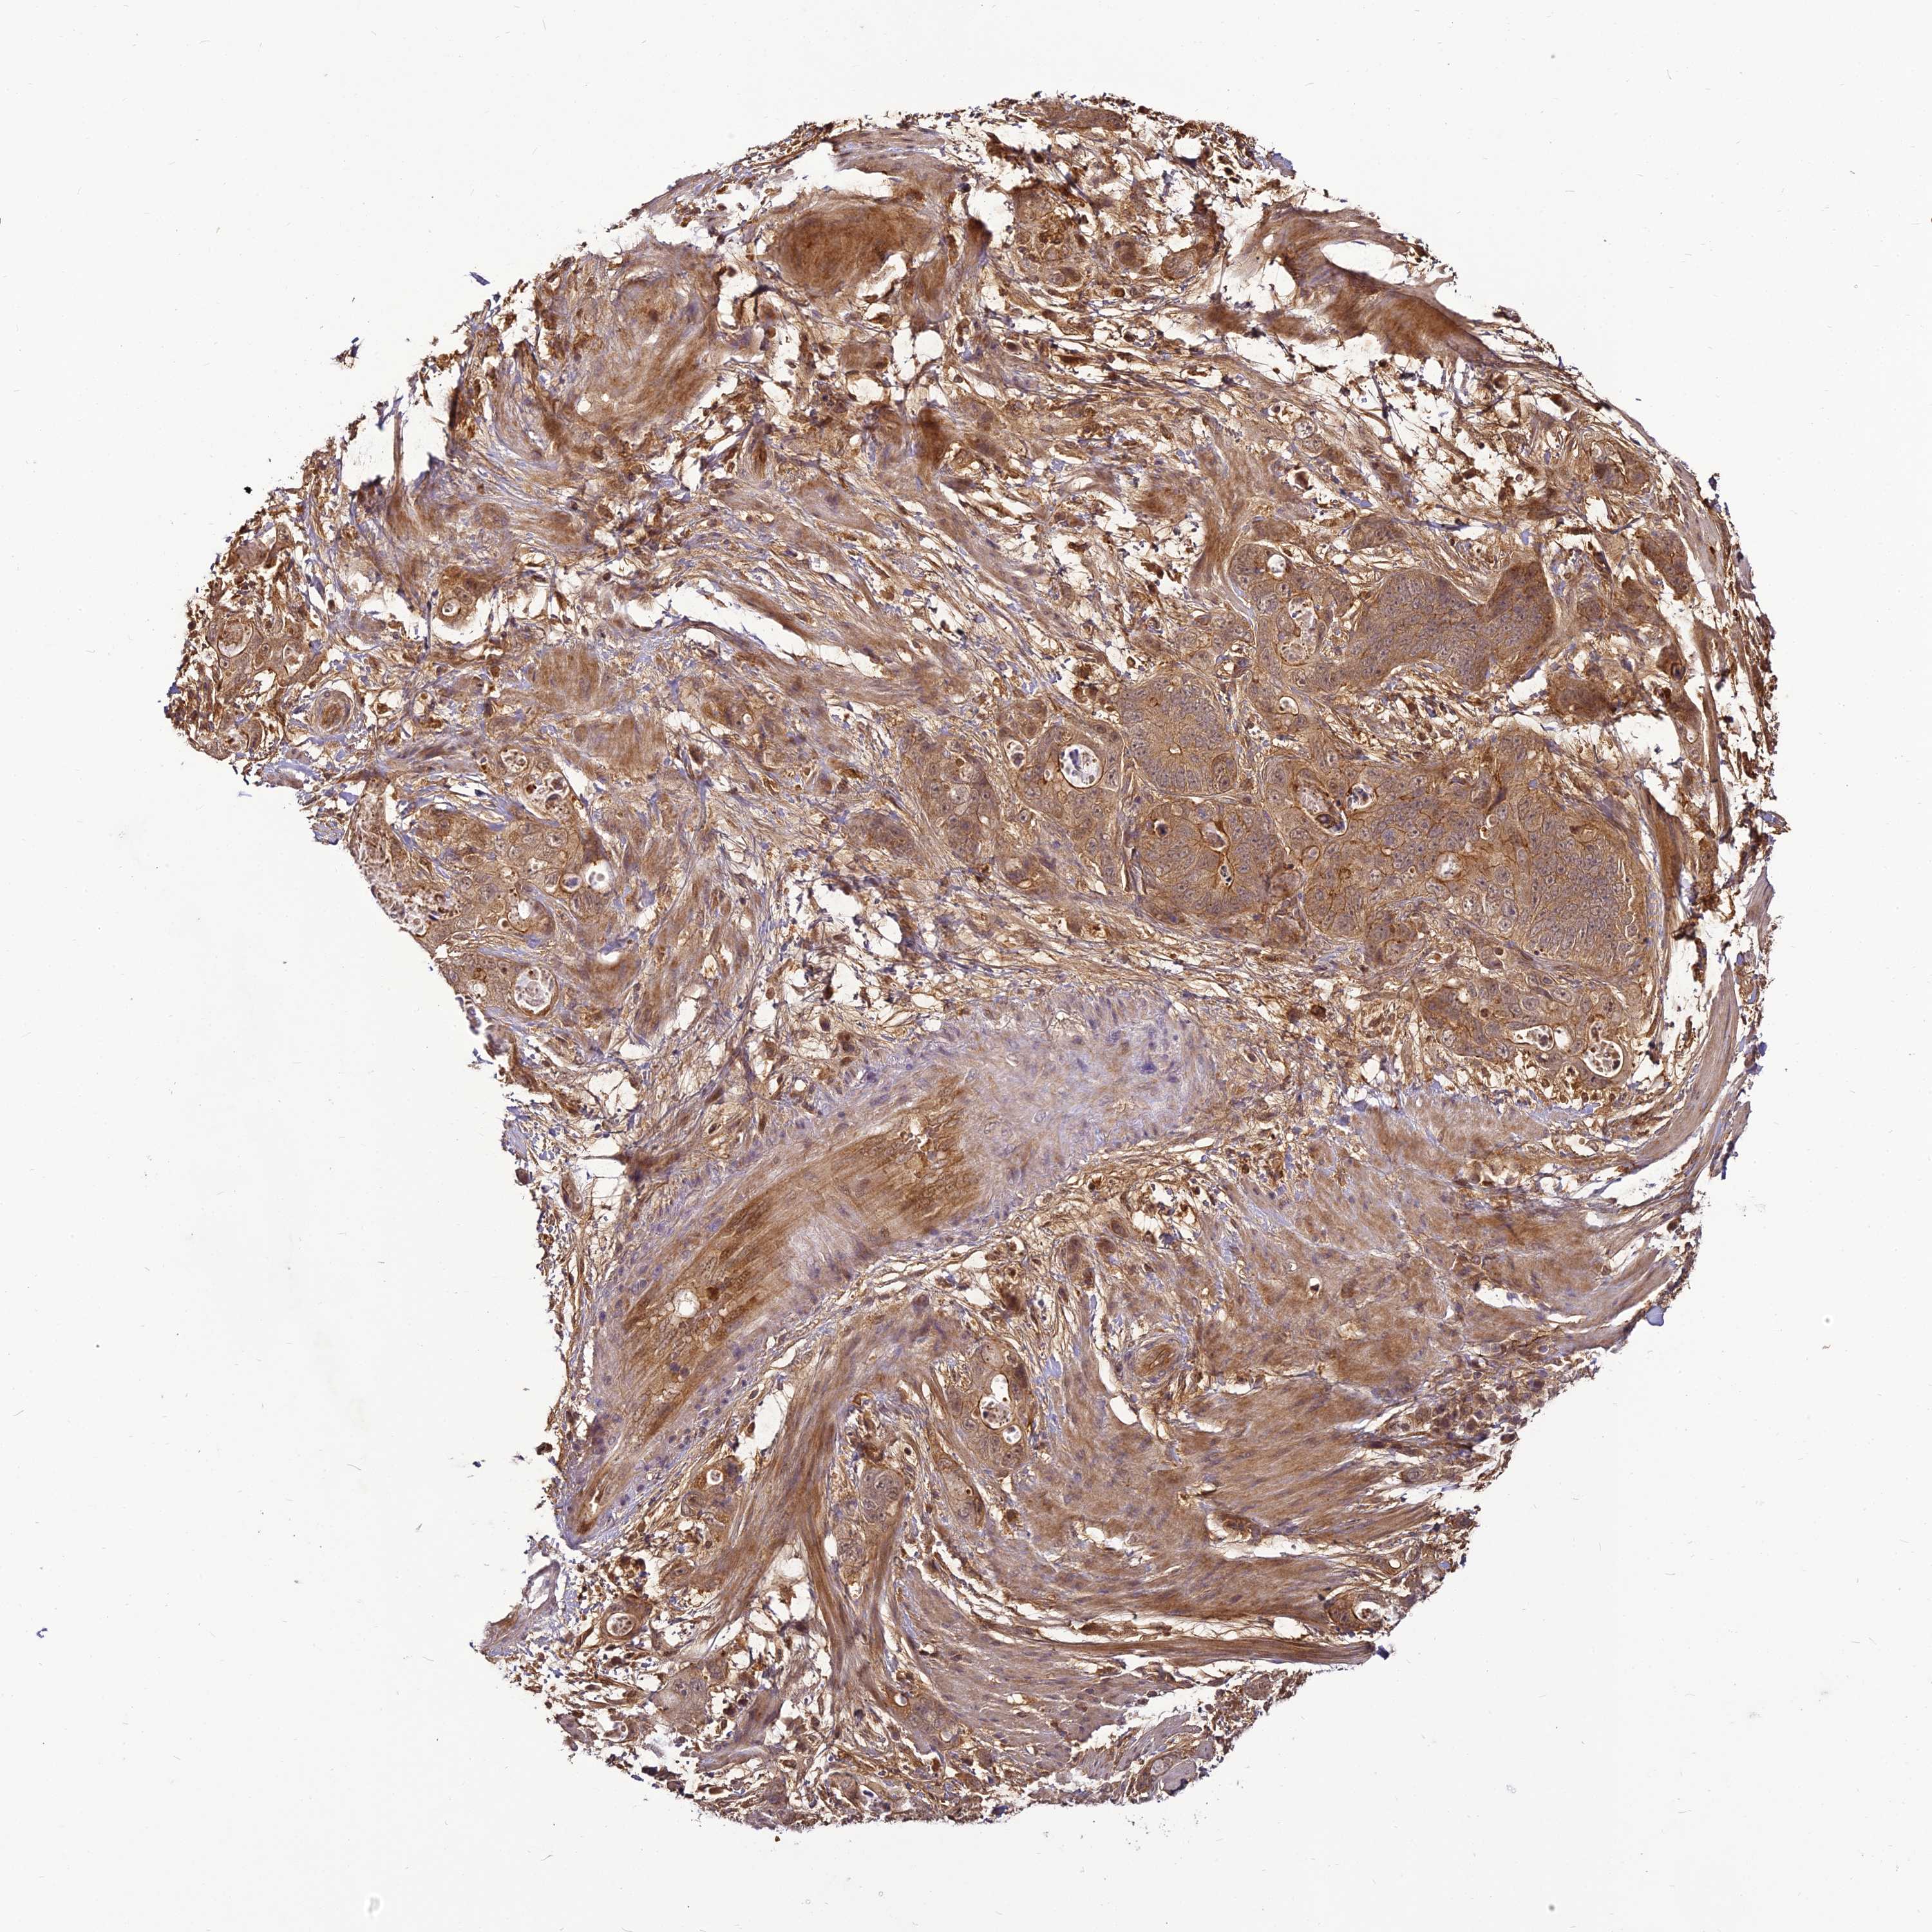

STOMACH CANCER - Protein expressioni

A mouse-over function shows sample information and annotation data. Click on an image to view it in a full screen mode. Samples can be filtered based on level of antibody staining by selecting one or several of the following categories: high, medium, low and not detected. The assay and annotation is described here.

Note that samples used for immunohistochemistry by the Human Protein Atlas do not correspond to samples in the TCGA dataset.

Antibody stainingi

Antibody staining in the annotated cell types in the current human tissue is reported as not detected, low, medium, or high, based on conventional immunohistochemistry profiling in selected tissues. This score is based on the combination of the staining intensity and fraction of stained cells.

Each image is clickable and will lead to virtual microscopy that enables deeper exploration of all samples and also displays staining intensity scores, fraction scores and subcellular localization as well as patient and tissue information for each sample.

Antibody HPA039911

Staining

High

Medium

Low

Not detected

Intensity

Strong

Moderate

Weak

Negative

Quantity

>75%

75%-25%

<25%

None

Location

Nuclear

Cytoplasmic/membranous

Cytoplasmic/membranous,nuclear

Adenocarcinoma, NOS